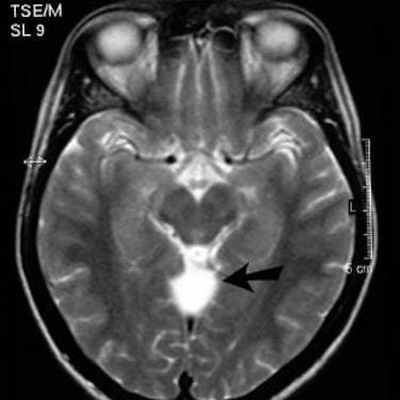

На изображениях они визуализируются в виде четко отграниченной полости с невидимыми стенками, оттесняющей прилегающие структуры, с сосдержимым характеризующимся паттерном аналогичным паттерну церебросиннальной жидкости (гиподенсивный при компьютерной томографии, гиперинтенсивный на Т2 взвешенных изображениях и гипоинтенсивный на Т1ВИ при магнитно-резонансной томографии). Они так же могу вызывать ремоделирование прилегающей кости.

Арахноидальные кисты на МРТ

МРТ оболочек головного мозга может показать арахноидальные кисты. Это врожденные внемозговые объемные образования, содержащие ликвор. Клинические проявления арахноидальной кисты зависят от локализации новообразования, но зачастую ее формирование протекает бессимптомно. Поскольку данное новообразование может вызывать нарушение ликвородинамики, оно часто сопровождается гидроцефалией. Крупные арахноидальные кисты иногда начинают сдавливать соседние участки головного мозга, вызывая атрофию и болевой синдром. Такие крупные кистозные образования требуют оперативного вмешательства. И здесь МРТ головного мозга позволит не только поставить точный диагноз, но и выработать план проведения операции. Если киста имеет малые размеры, тактика её лечения будет сводиться к наблюдению. Невролог или нейрохирург в такой ситуации будет рекомендовать пациенту делать МРТ головного мозга один раз в 6 месяцев, чтобы не пропустить момент роста.

МРТ-диагностика арахноидальной кисты

В клинической практике встречаются случаи, при которых арахноидальная киста развивается бессимптомно. По этой причине при отсутствии выраженных проявлений болезни зачастую только МРТ способна выявить ее на первоначальной стадии. В ходе магнитно-резонансной томографии на патологию указывает скопление ликвора (спинномозговой жидкости) в области паутинной (арахноидальной) оболочки головного мозга. Появление данной пустоты вызвано расщеплением оболочки в головном мозге на несколько слоев.